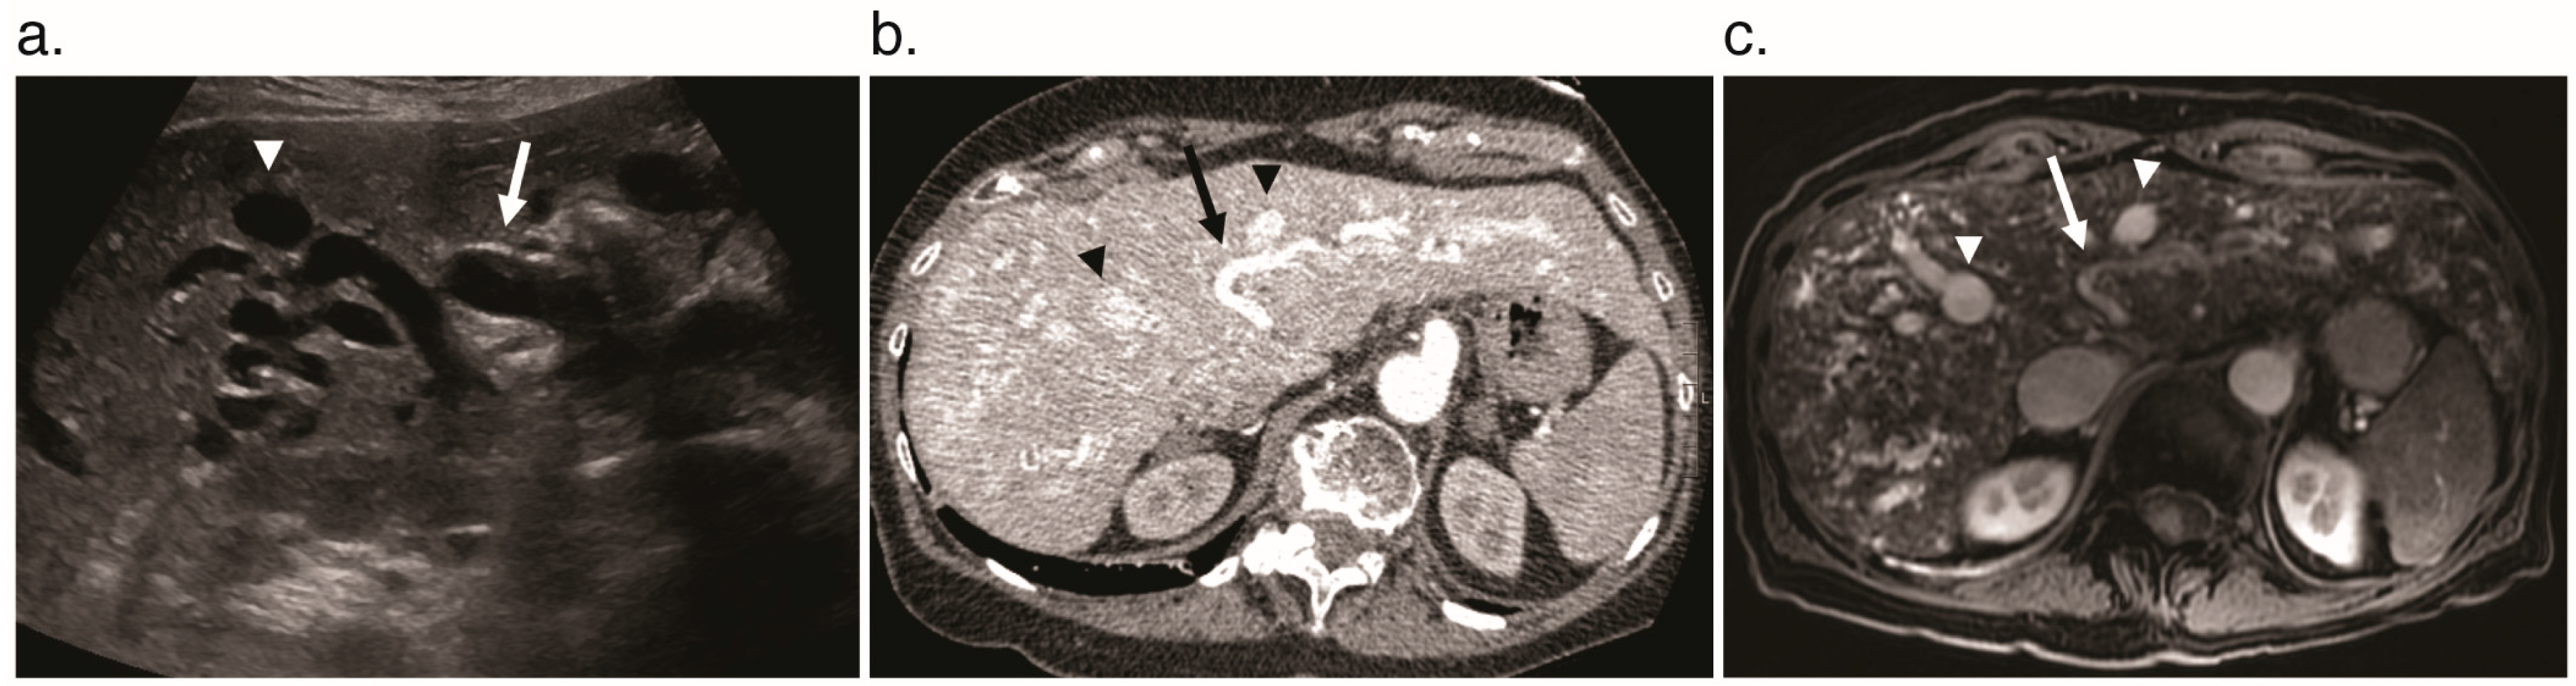

6.1. Pseudocirrhosis

6.2. Focal Nodular Hyperplasia

6.3. Cholangiopathy